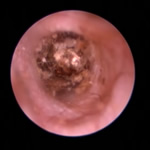

鼓膜とその周囲の病気

角化症、脂漏症という生まれつきの体質を持ったワンちゃんは耳垢が多くなりがちです。また、角化症、脂漏症の長毛種となれば、耳の中に毛が生えた犬種も多く耳道から耳垢を排泄しにくくなります。それらが原因で耳に汚れがたまります。また長毛種はトリミングに行く回数も多く、耳を洗う機会が多くなります。こんな負の連鎖があり、いずれも耳を悪くする大きな原因になります。その全ての要因に対処しなければ耳の病気は解決しません。写真は鼓膜手前に耳垢や毛が蓄積し、通常の耳洗浄ではきれいにできない状態です。セカンドオピニオンで来院されるワンちゃんで最も多い病気の1つです。